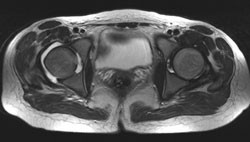

Åtte dager etter innleggelsen utviklet kvinnen høyresidige pleurittiske smerter. Røntgen thorax viste to avrundede lesjoner i høyre lunge, en med luft-væske-speil (fig 1). Påfølgende CT thorax viste multiple kaviteter i lungene, forenlig med abscesser. Øre-nese-hals-undersøkelse dag 10 viste gråbrune belegg på tonsillene, men ingen tegn til peritonsillær abscess. Ekkokardiografi dag 13 viste ingen tegn til endokarditt.

Lungetuberkulose med kavitet var her en differensialdiagnose, men tilstanden ble oppfattet som mononukleose og sekundærinfeksjon med F necrophorum, med multiple metastaserende lungeabscesser.